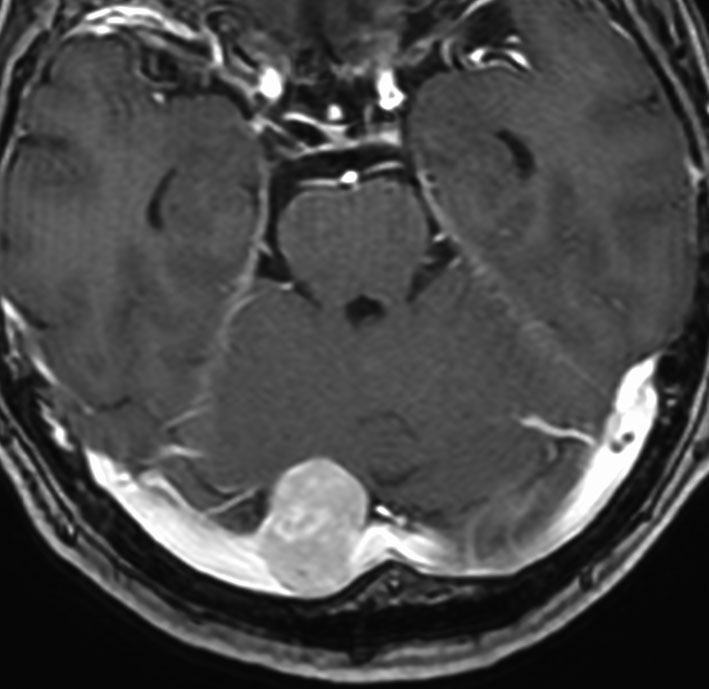

左は,造影剤を使ったガドリニウム増強MRIです。腫瘍が白く丸く見えます。右はフレア画像で,腫瘍の周囲の脳浮腫(脳のはれ)です。左前頭葉が,かなり強くはれています。この腫瘍は小さいのですが,脳のはれが強すぎるので手術摘出したほうがいいです。浮腫が悪化すると,てんかん発作や認知機能低下がでる可能性があります。